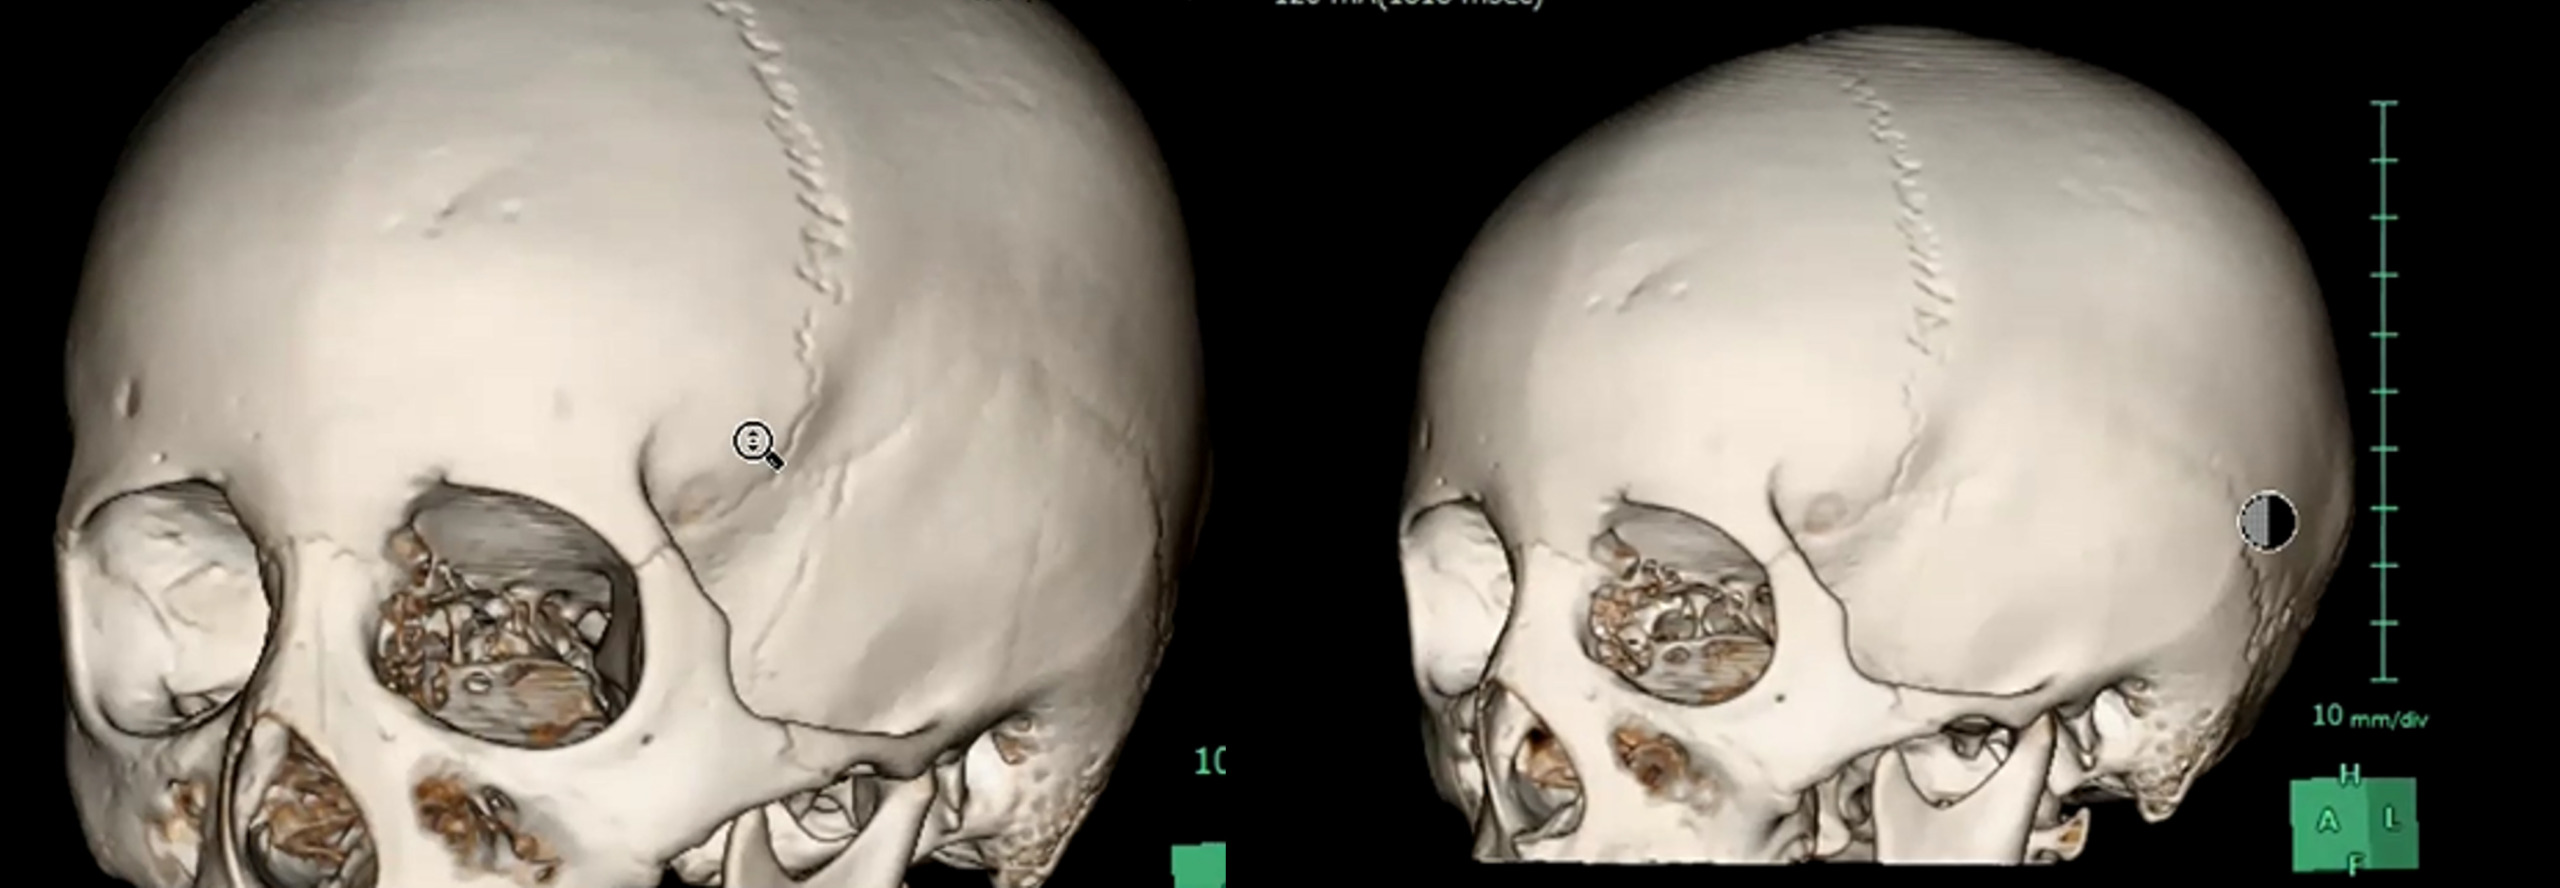

この時に最初のCT画像を振り返ると、実は”3D画像”がありました 。

画像がこちらです。

受傷部側の画像ですが、なにか気づきましたか?

受傷部の骨が一部陥没していることがわかります。

これを踏まえて、もう一度、骨条件の画像を確認しました。

一見すると異常が分かりにくい画像でも、3D画像を確認することで骨折の存在が明確になりました。

小児は骨が柔らかいため、外板のみが折れて陥没し、完全骨折に至らず所見が目立ちにくいことがあります。出血も初期は少量で、時間経過とともに明瞭化しました。本症例は外傷性陥没骨折、外傷性くも膜下出血・硬膜下血腫、脳挫傷と診断されました。